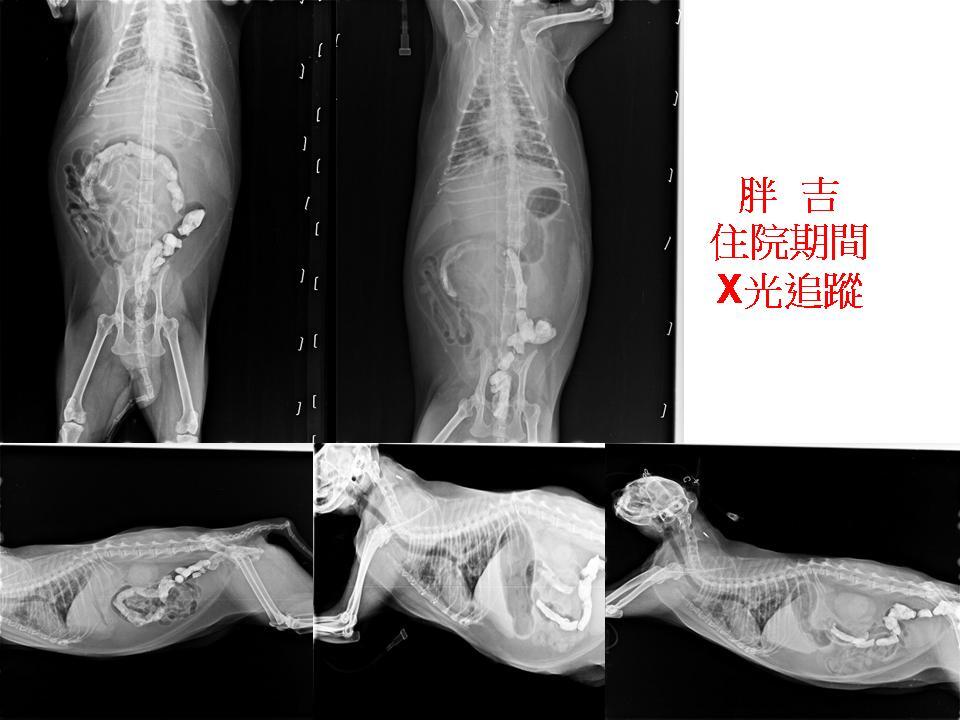

主題: 口炎、腎衰胰臟炎的胖吉 申請者姓名: 臺北市支持流浪貓絕育計劃協會 花色: 申請日期: 2019-01-25 10:09:37 申請者部落格: 申請者臉書網址: 所在縣市/合作醫院: 台北市/極光動物醫院 治療費用: 23454元 需求人數: 50人 已結案 (2024-05-31 18:36:05) 報名人員: 荳妹媽咪(已付款)、荳妹媽咪(已付款)、酷比 x2(已付款)、wgs(已付款)、穆穆(已付款)、阿草 x2(已付款)、陳 小豬(已付款)、海郁(已付款)、賴小虎 x2(已付款)、Lovly Queenie(已付款)、Clio x2(已付款)、Lovly Queenie(已付款)、Lovly Queenie(已付款)、Penny Ko(已付款)、Doris Chen(已付款)、潘亮岑、林螢逸(已付款)、Esther(已付款)、Esther(已付款)、愛肝(已付款)、玉玲瓏(已付款)、Zoe Peng x2(已付款)、李大胖(已付款)、陳派佐 x2(已付款)、Angel Lin(已付款)、Monica Wang x2(已付款)、濃 x2(已付款)、Ingrid198li(已付款)、Yen-Yuan Wang(已付款)、洪凱威 x2(已付款)、Sol x4(已付款)、apple(已付款)、Chang Fu(已付款)、Juen-Nien Lin x5(已付款)、Kathy Lee(已付款)、 候補人員: 動物病情說明: 胖吉來自台中一個廢棄眷村,原本的餵養者不但沒有給她好的照顧飲食,連生病也沒有帶去就醫,胖吉因此非常瘦弱,病得很慘,協會緊急帶她就醫,經檢查,她的健康出了很大問題,有愛滋、口炎、黃疸、慢性腎病、肝炎,還因肝指數異常(ALT大於1000)而造成癲癇症狀,治療期間經歷兩次輸血、上食道餵管才逐漸好轉。

因胖吉是愛滋貓咪原故,健康情況易有變數,週一(12/10)晚班照顧人員發現胖吉呼吸急促,於是提前一天帶胖吉回診,住院期間胖吉一直住在氧氣室,且胰臟炎併發肺炎,用藥治療後狀況並無好轉。

血氧檢查無得到有效結果,再進行X光拍攝,發現胖吉肺部有些白點,目前研判是肺部感染,先留院施打靜脈注射抗生素。